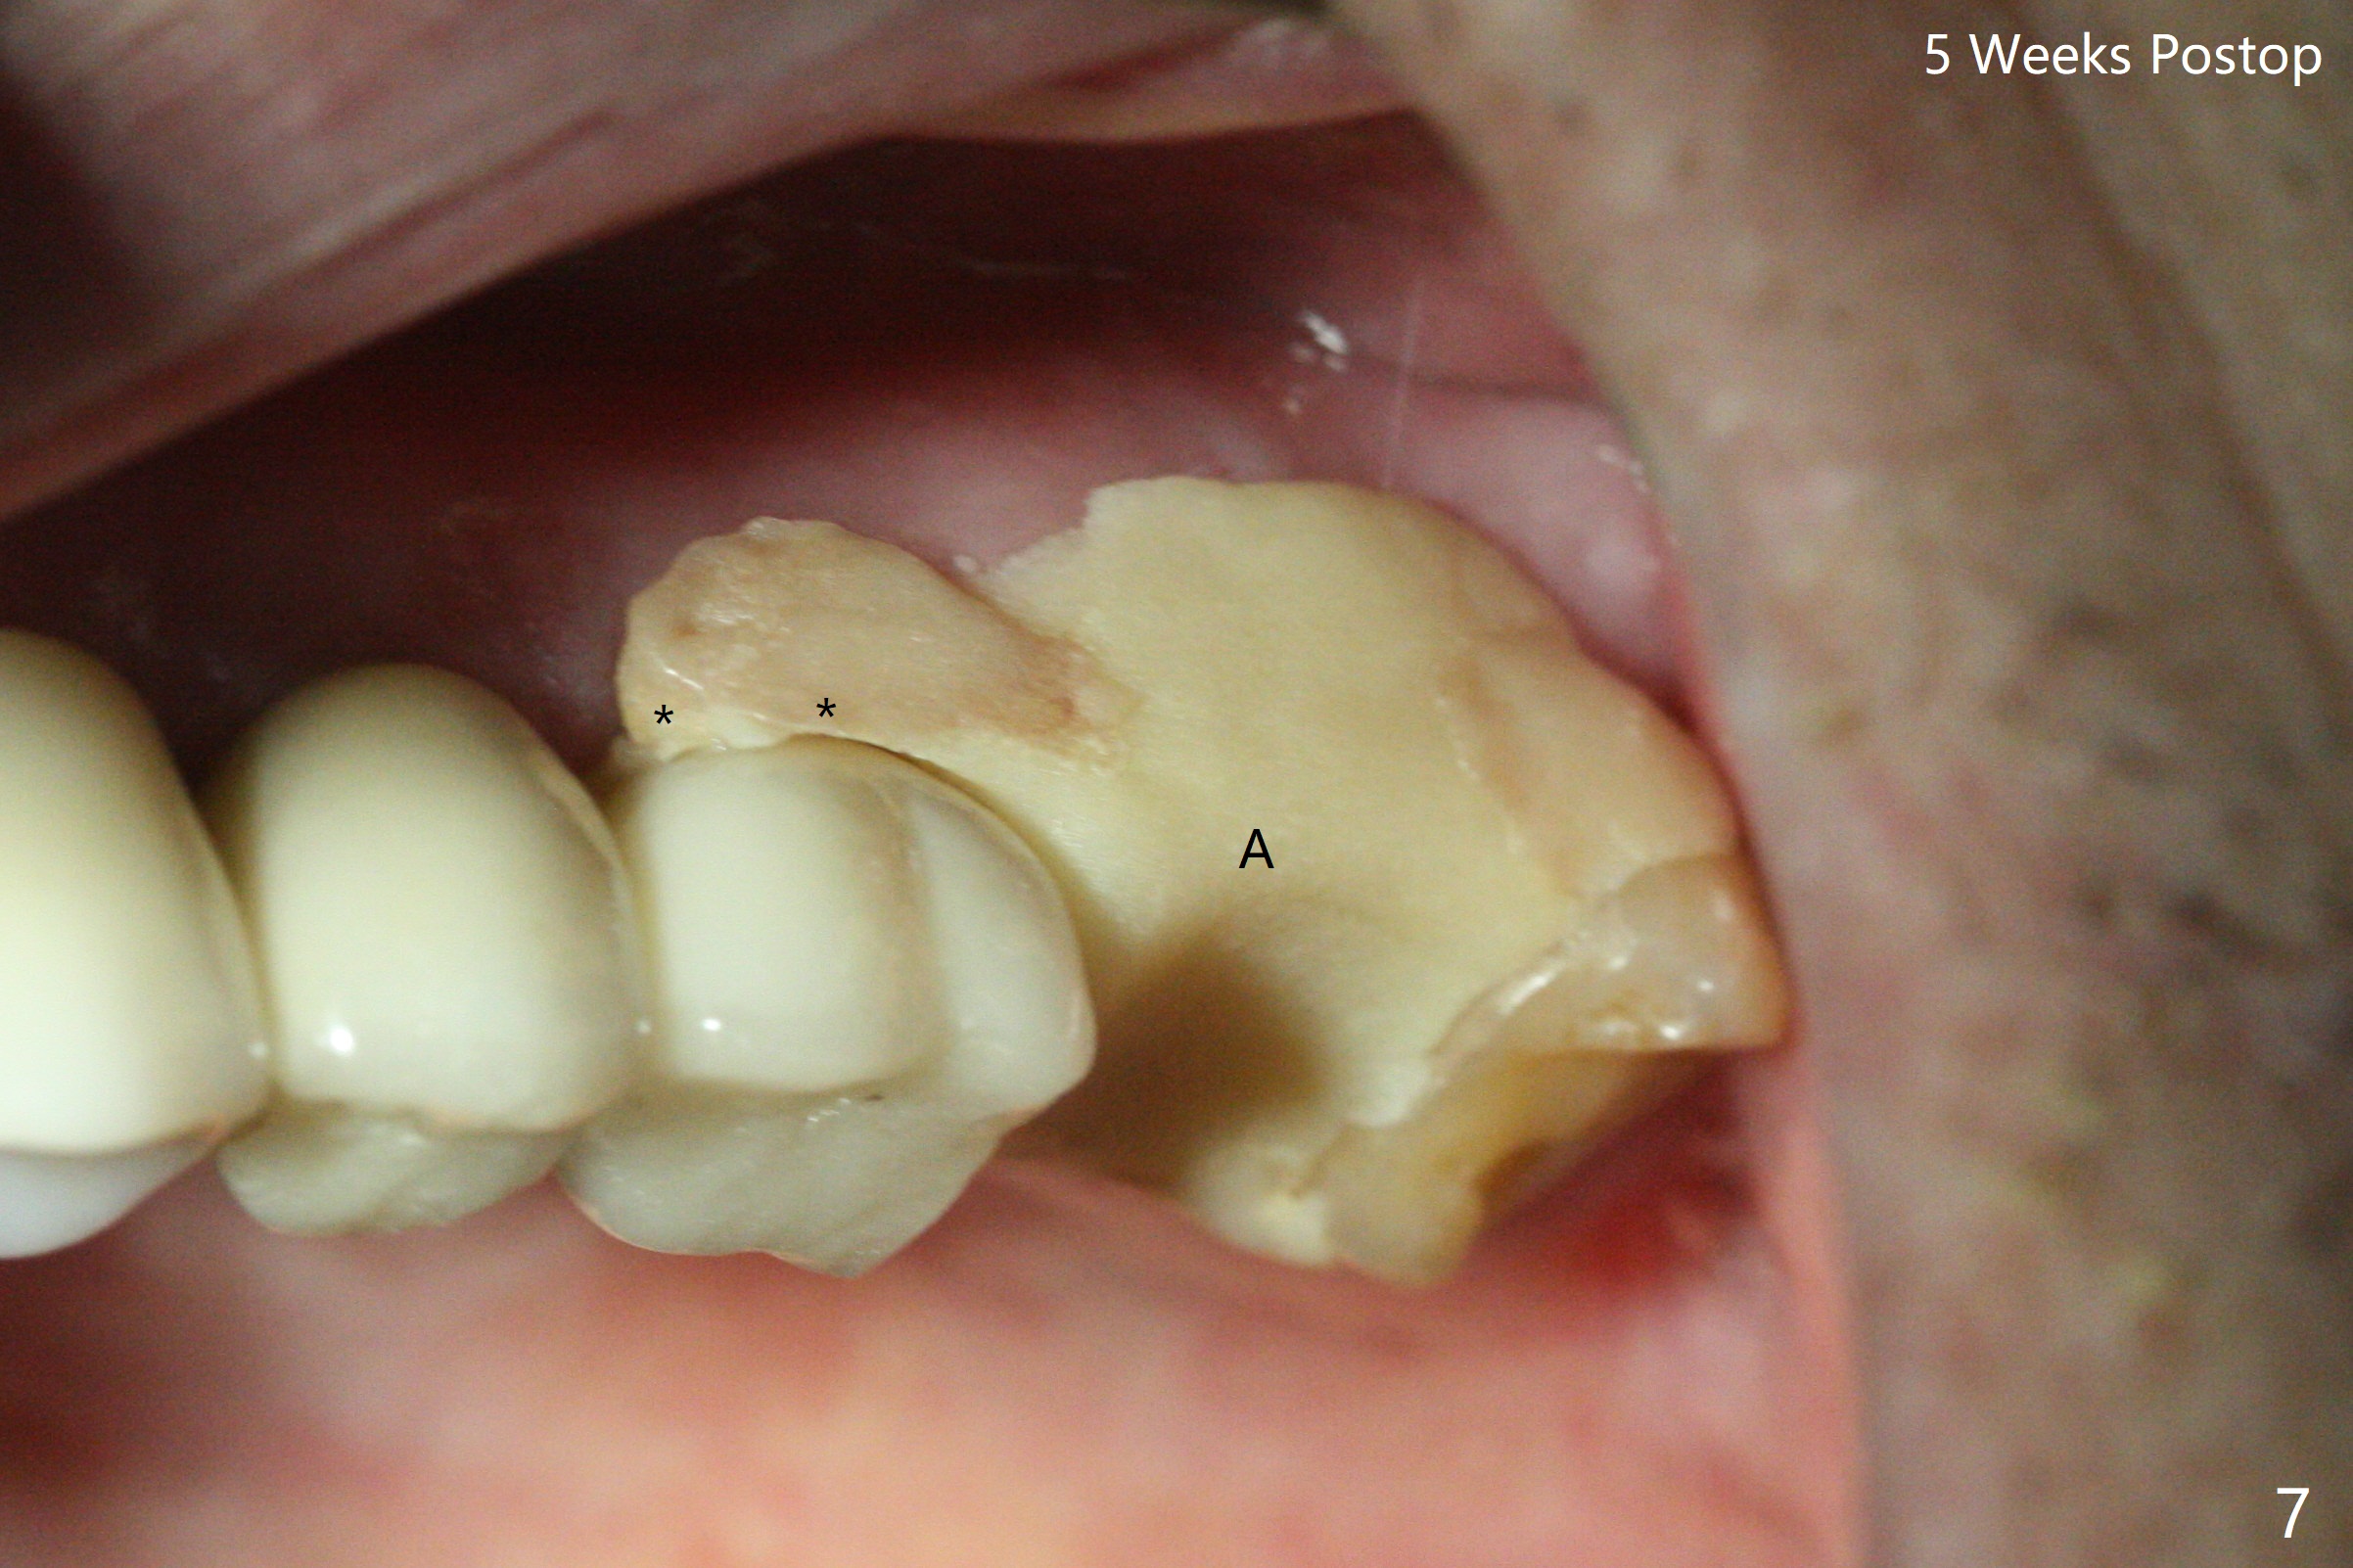

The 7x14 mm implant at #15 of a 89-year-old man is found to be loose ~ 1 year post cementation (Fig.1). After implant removal and debridement, bone graft is placed (Fig.2 G); the mesiocervical caries of the 3rd molar is removed, but not filled (*). With collagen membrane fixed with Chromic gut suture (Fig.3), setting acrylic is applied in the edentulous area, including the mesiocervical cavitation of the 3rd molar (Fig.4) for further retention. Bone graft gets lost following socket preservation at #31 with periodontal dressing. When the bone graft matures, a new implant (Fig.6 green) will get primary stability from the native bone, i.e., coronal to the sinus floor (Fig.5 F). The acrylic dressing (Fig.7 A) with a portion locking to the undercut of the neighboring crown (*) remains in place 5 weeks postop. When the dressing is cut off, the bone graft is exposed with odor (Fig.8,9 *). Periodontal dressing is applied. The distolingual portion of it gets lost due to brushing a day later. When he returns, the dressing is removed (Fig.10). It appears that the growing in gingival margin is pushing the bone graft out. A moment later after just a few rounds of swallowing, more graft is lost (Fig.11). We would love to leave the wound open, but the senior citizen complains of air leaking and requests reapplication of periodontal dressing. The bone graft is almost gone when the 2nd periodontal dressing is removed nearly 2 months postop (Fig.12). The tooth sensitivity disappears when MO caries is taken care of. The socket has a dimple 5 months postop (Fig.13), although it is filled with bone graft (Fig.14). Due to low bone density (~500 HU), sinus lift is required for implant stability with PRF (Fig.15). In fact the lab chooses not to do sinus lift.